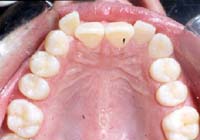

Treatment Time: 6 months

Aligners: 12 Upper, 7 Lower